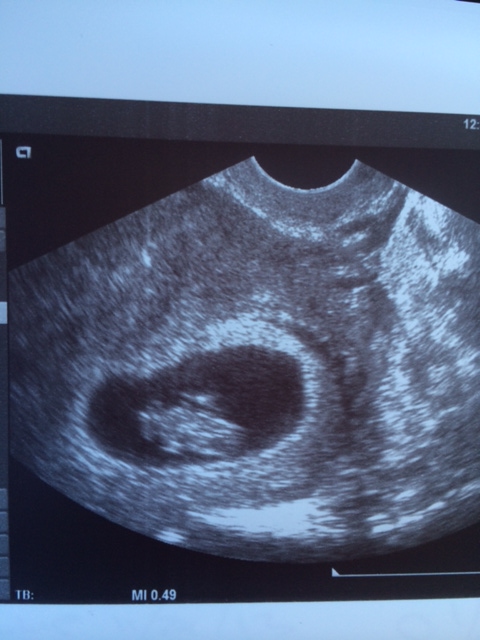

I then sent him my 7 1/2 week ultrasound and he changed his prediction to girl now, see the difference, the placenta has spread out more to the left now.

Attachment 16466